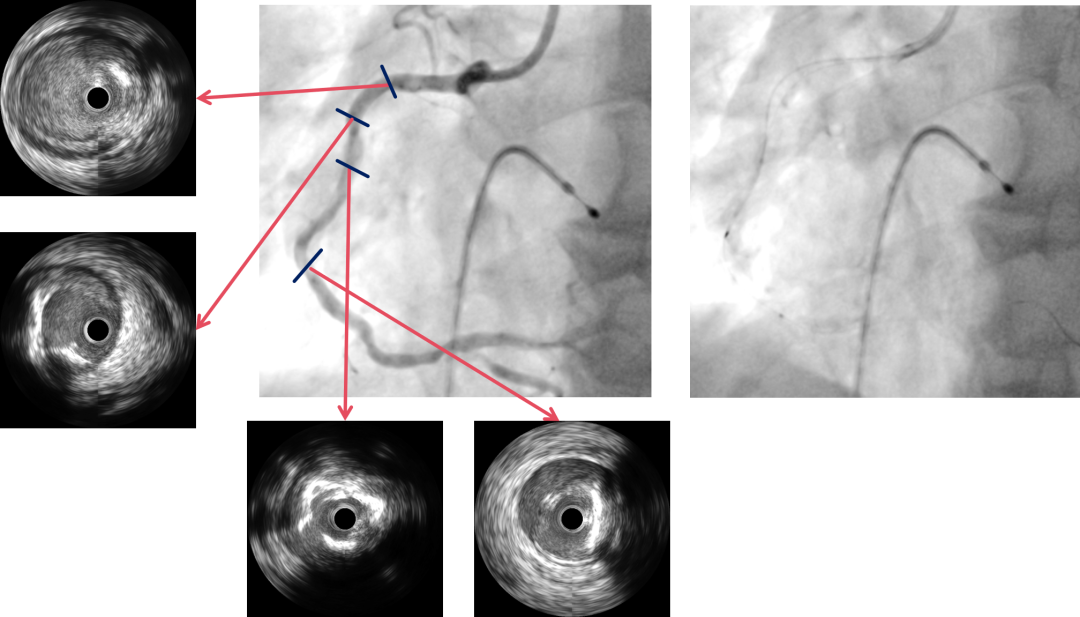

冠脉造影

PCI过程-冠状动脉旋切(轨道旋磨)术-1

IVUS导管无法通过,微导管辅助下,将旋磨导丝置于RCA远端,应用1.0mm磨头以13万转反复旋磨钙化病变处(每次15秒,磨头推进速度不超过10 mm/s)

PCI过程-冠状动脉旋切(轨道旋磨)术-2

微导管辅助下,将旋磨导丝置于RCA远端,应用1.0mm磨头以13万转反复旋磨钙化病变处(每次15秒,磨头推进速度不超过10 mm/s)

PCI过程-冠状动脉旋切(轨道旋磨)术-3

共计旋切170秒,术后,狭窄较前减轻

PCI过程-IVUS

PCI过程-球囊PTCA

IVUS可见钙化变薄、环形钙化断裂